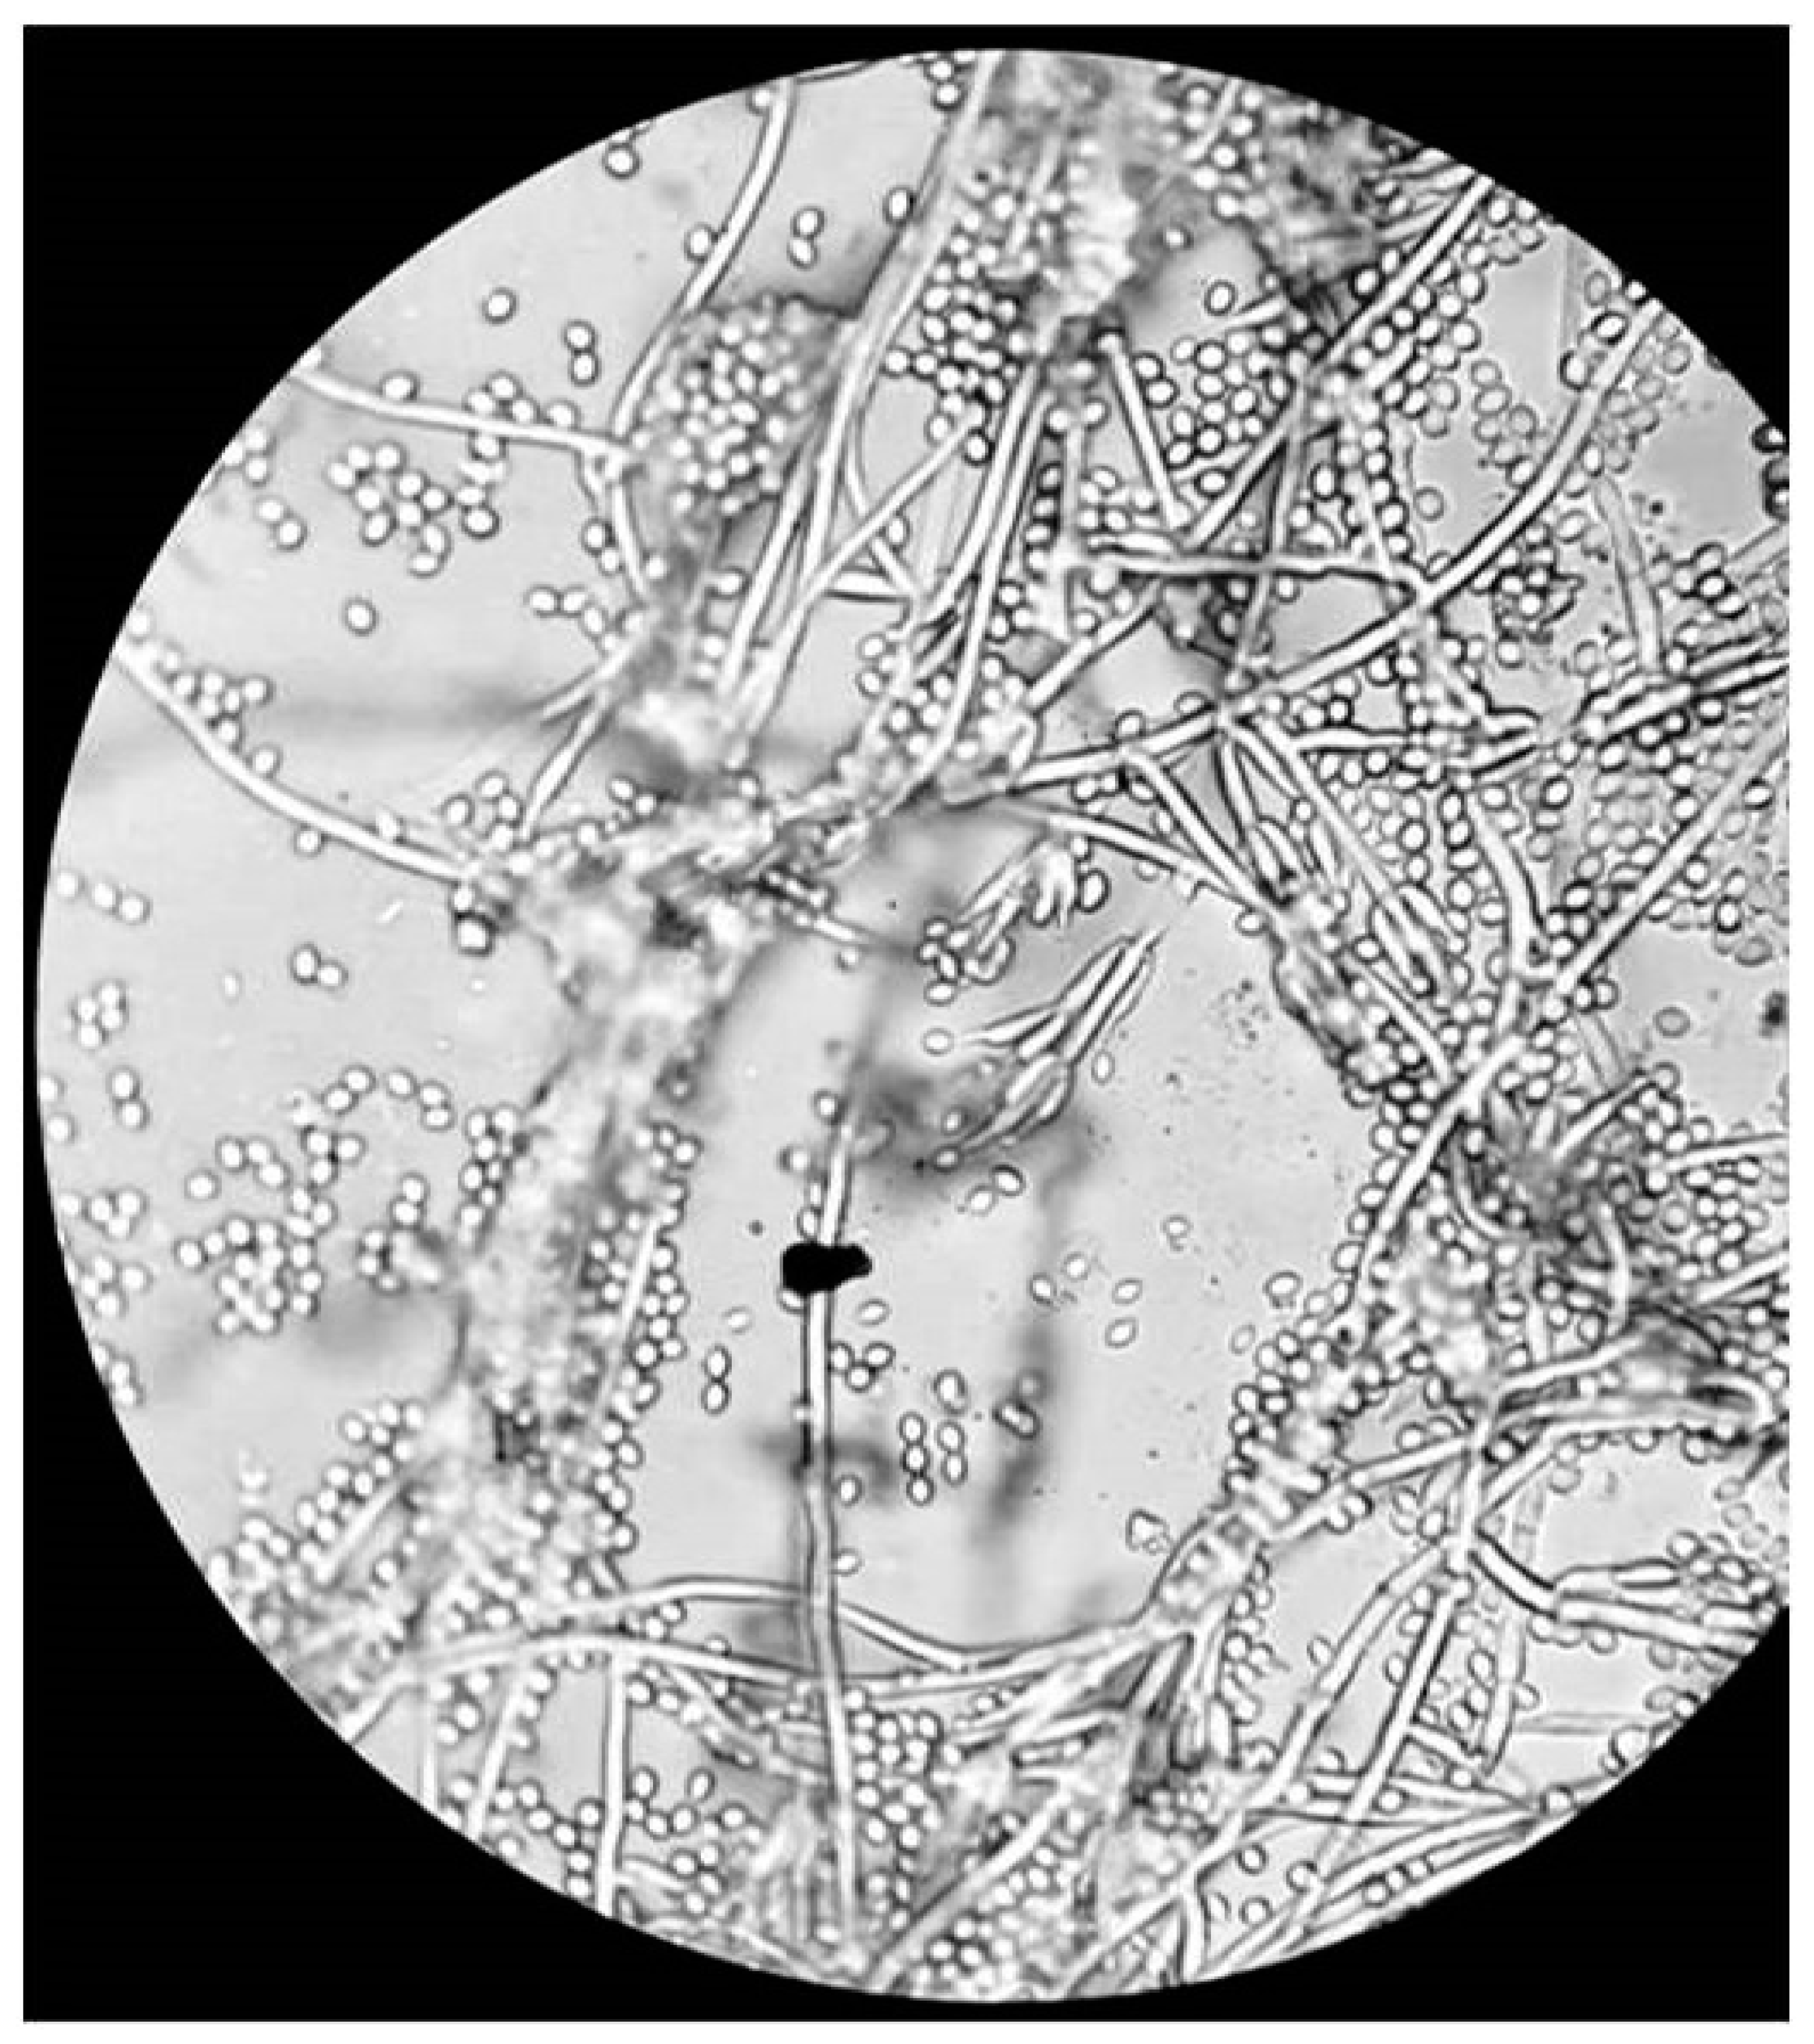

2.1. Culture

3. Results